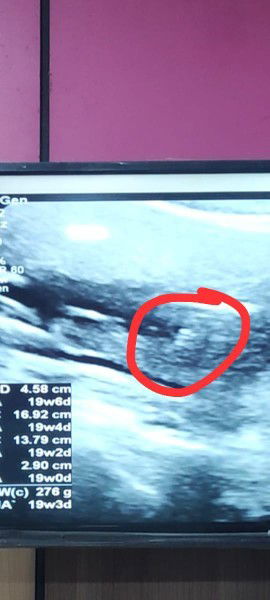

Gender Scan (Boy or Girl)

Hi mommies! Saja nak test mata mommies semua. Agak-agak baby boy ke girl? Just for fun. Saya pun tak kisah boy or girl, janji sihat hehe. Saya pergi dua tempat berbeza untuk scan, dua-dua bagi jawapan berbeza. Based on scan photo ni, mommies rasa baby boy ke girl? #firsttimemom #genderscan ##firstbaby #firstmom #ingintahu #BoyorGirl